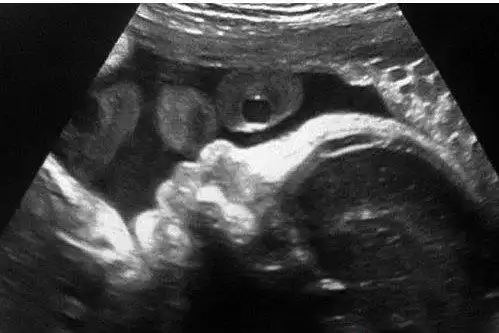

辨别胎儿性别有方法,b超单上一清二楚,再也不用求医生了!

b超照

胡杏儿晒胎儿b超照 宝宝小脚丫超可爱(图)

夏奇拉挺大肚晒b超宝宝照 欲在巴塞罗那建新居